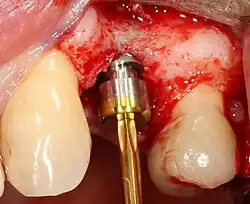

A series of slow-speed drills create and gradually enlarge a site in the jaw for the implant to be placed. The hole is called an osteotomy.

Once the bone is exposed, a series of drills create and gradually enlarge a site (called an osteotomy) for the implant to be placed.

The implant fixture is turned into the osteotomy. Ideally, it is completely covered by bone and has no movement within the bone.

Placing the implant

Most implant systems have five basic steps for placement of each implant:[28]: 214–221

1. Soft tissue reflection: An incision is made over the crest of bone, splitting the thicker attached gingiva roughly in half so that the final implant will have a thick band of tissue around it. The edges of tissue, each referred to as a flap, are pushed back to expose the bone. Flapless surgery is an alternate technique, where a small punch of tissue (the diameter of the implant) is removed for implant placement rather than raising flaps.

2. Drilling at high speed: After reflecting the soft tissue, and using a surgical guide or stent as necessary, pilot holes are placed with precision drills at highly regulated speed to prevent burning or pressure necrosis of the bone.

3. Drilling at low speed: The pilot hole is expanded by using progressively wider drills (typically between three and seven successive drilling steps, depending on implant width and length). Care is taken not to damage the osteoblast or bone cells by overheating. A cooling saline or water spray keeps the temperature low.

4. Placement of the implant: The implant screw is placed and can be self-tapping;[50]: 100–102  otherwise, the prepared site is tapped with an implant analog. It is then screwed into place with a torque controlled wrench[54] at a precise torque so as not to overload the surrounding bone (overloaded bone can die, a condition called osteonecrosis, which may lead to failure of the implant to fully integrate or bond with the jawbone).

5. Tissue adaptation: The gingiva is adapted around the entire implant to provide a thick band of healthy tissue around the healing abutment. In contrast, an implant can be "buried", where the top of the implant is sealed with a cover screw and the tissue is closed to completely cover it. A second procedure would then be required to uncover the implant at a later date.